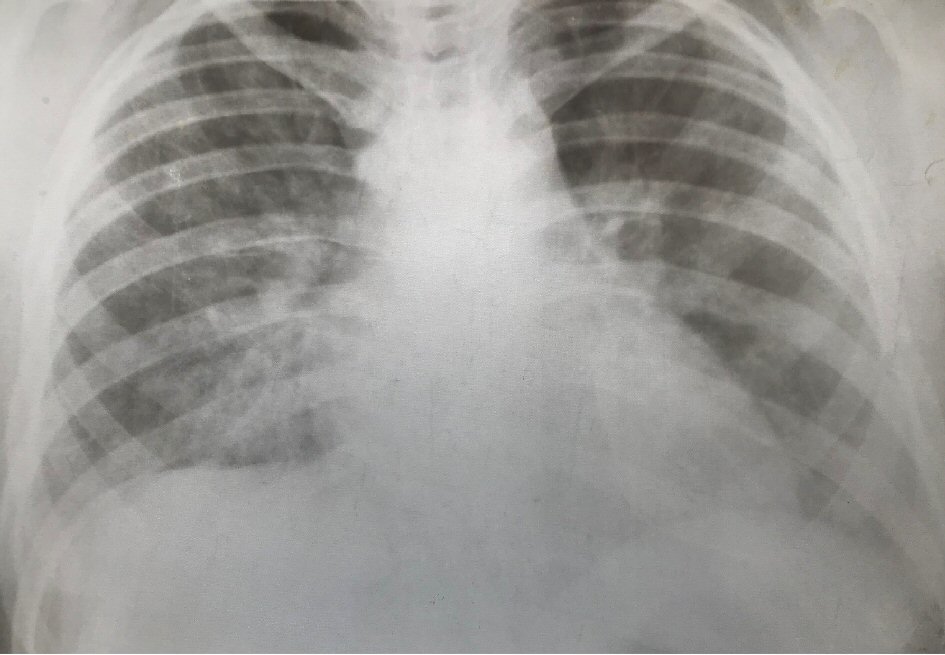

The chest X-ray showed bilateral diffuse opacities and pleural effusion on the right lower lobe (Fig. 2) that was confirmed with portable bedside thoracic echography. In cardiac echography, the function of left and right ventricle was normal, the size was normal and pericardia effusion was not noticed. Level of C-reactive protein was high with value of 120 mg/L (normal range: 1 - 8 mg/L) 72 h after the admission and the treatment with antibiotic was continued. Blood culture showed no pathogen. The culture of tracheobronchial secretions from endotracheal tube has not identified microbial growth.

![]() Click for large image | Figure 2. The chest X-ray. |

Diagnosis of pediatric acute respiratory distress syndrome (PARDS) as consequence of non- cardiogenic pulmonary edema was made of severe respiratory insufficiency with hypoxemia (PaO2/FiO2 = 102) and diffuse bilateral opacities on chest X-ray. The refractory hypotension was persistent although the treatment with liquids, calcium, vasopressors infusion and intralipid.